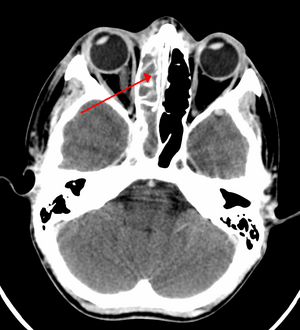

| A CT scan showing sinusitis of the ethmoid sinus | |